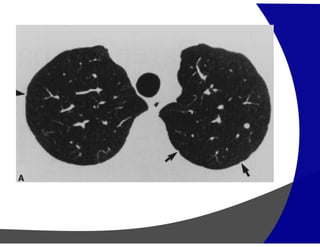

Cistos Áereos – Areas de menor atenuação

Enfisema

Cistos pulmonares (LAM, LIP, Histiocitose de células de Langerhans)

Bronquiectasia

Faveolamento

PADRÃO DE REDUÇÃO DE ATENUAÇÃO

“Manchas pretas”

Parasseptal

Centrolobular Panlobular

Enfisema Pulmonar

Cistos Aéreos

(Granuloma Eosinofílico ou Histiocitose

Pulmonar de Células de Langerhans)